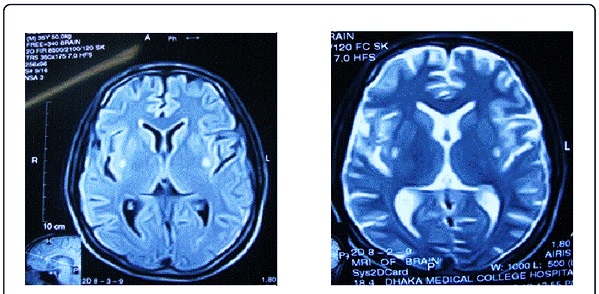

- Магнитно-резонансная томография (МРТ). Устанавливается степень поражения головного мозга, визуализируются очаги некроза и их параметры.

- Компьютерная томография (КТ). Дополнительный метод диагностики, если МРТ полностью не прояснила преобладающую клиническую картину.